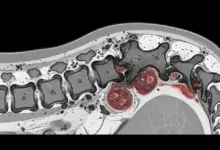

- Exames de imagem: radiografia, tomografia computadorizada e ressonância magnética (método mais sensível para partes moles, disco e medula).